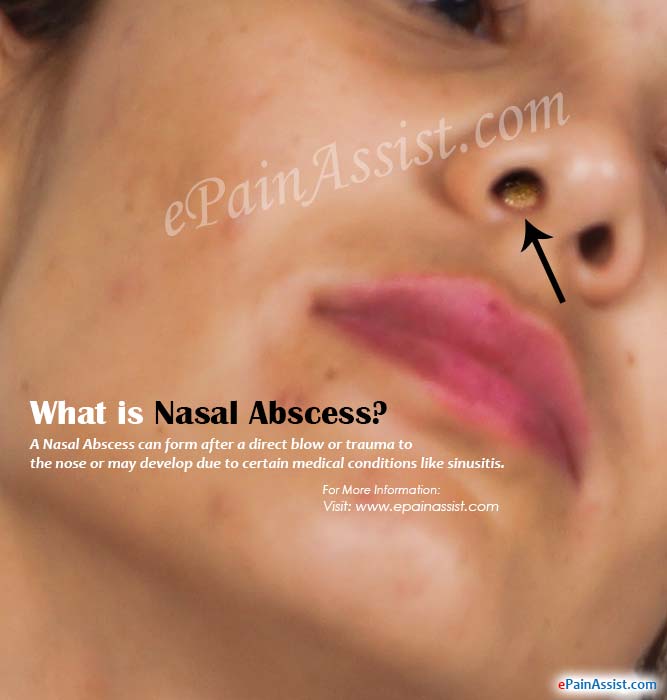

What is Nasal Abscess & How is it Treated?